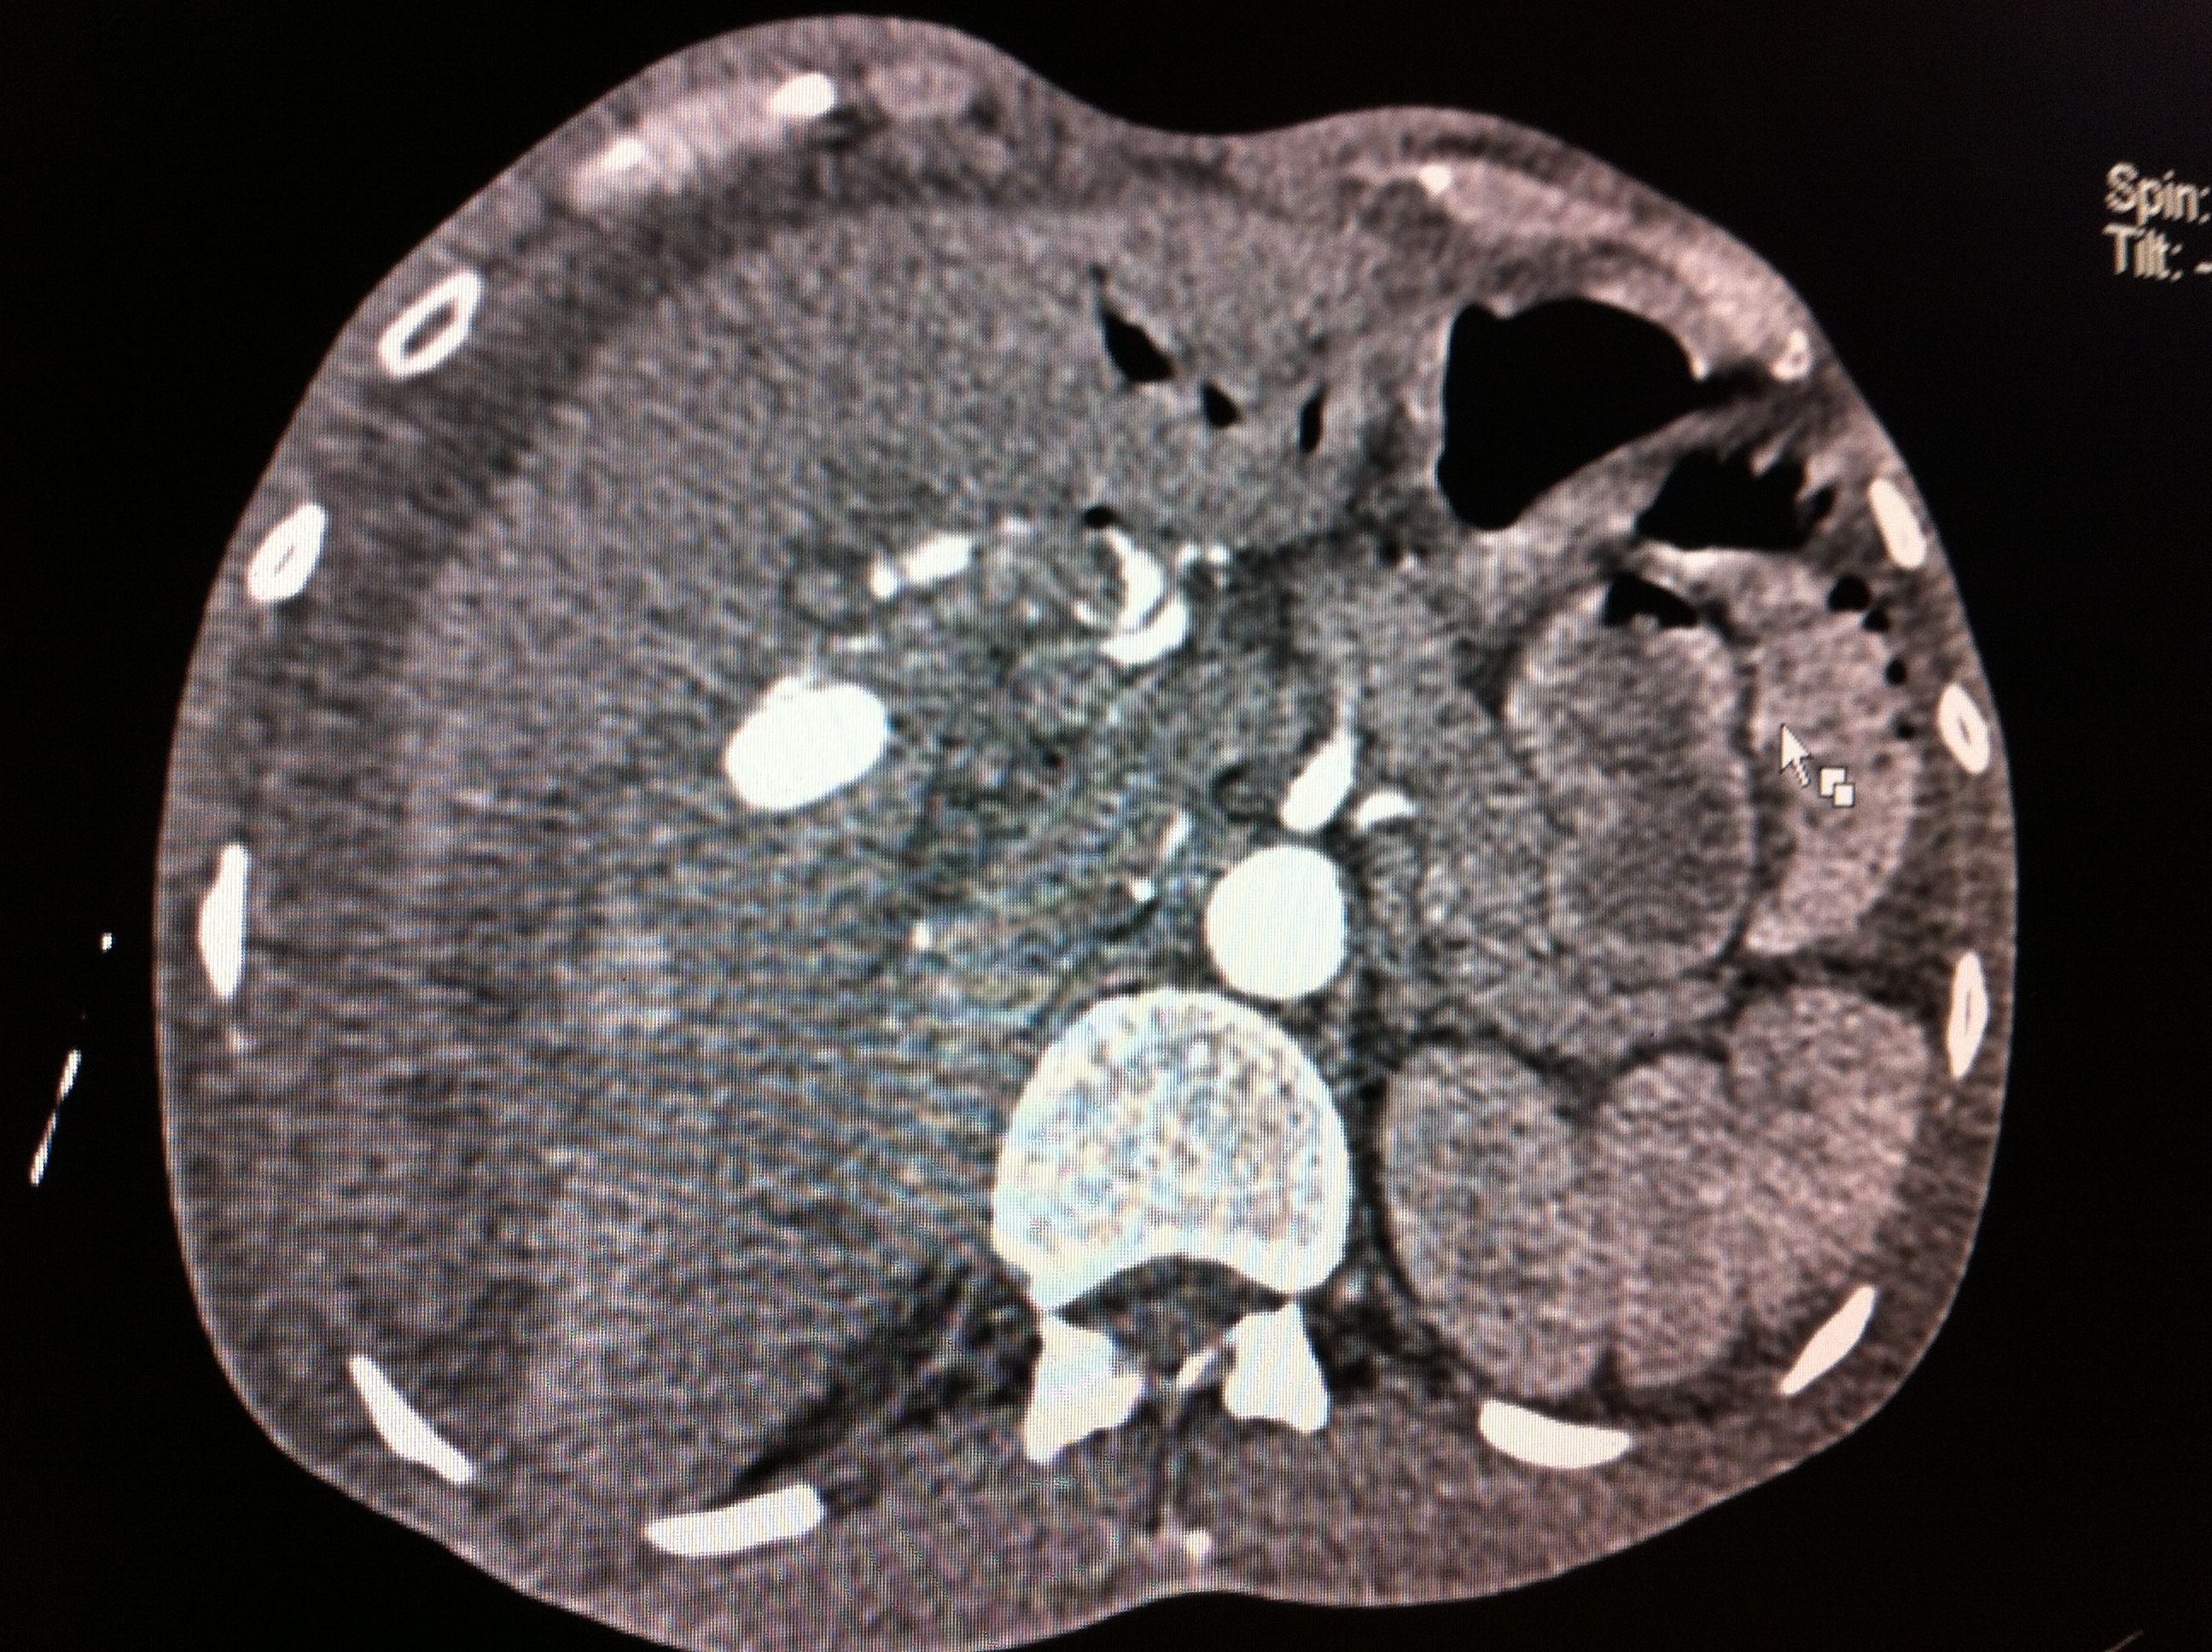

Endoscopic Retrograde Cholangio-Pancreatography (ERCP) has advantage of having bothdiagnostic and therapeutic utility and most common indication for endoscopic sphinterotomyis choledocholithiasis. Therapeutic ERCP is quite often associated with complications, mostcommon being acute pancreatitis followed by bleeding. Most common source of bleedingis small branches of pancreaticoduodenal artery (PDA) which lie close to papilla. We reporta rare case of leaking right hepatic artery pseudoanerysm following clearance of commonbile duct (CBD) stones by ERCP presenting with shock and upper GI bleed.